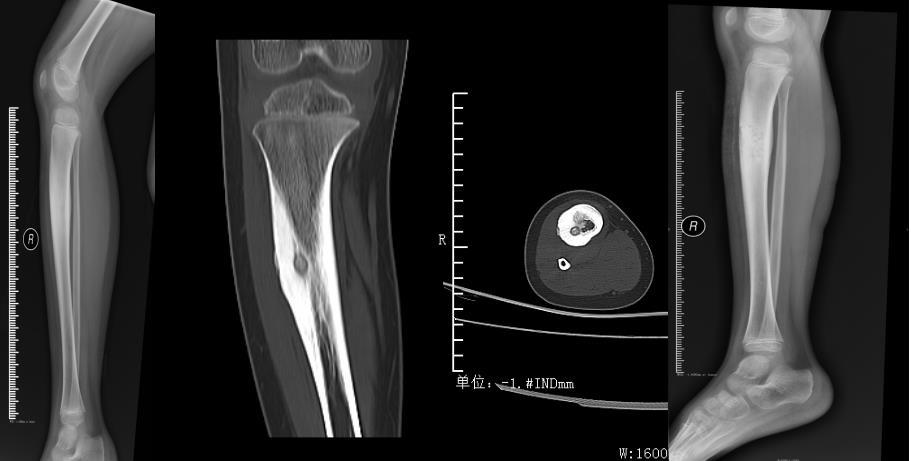

骨样骨瘤,在广州、深圳等多家三级医院辗转就诊3年多均未能明确诊断,到我科首次就诊得以明确诊断,手术治疗后很快康复。